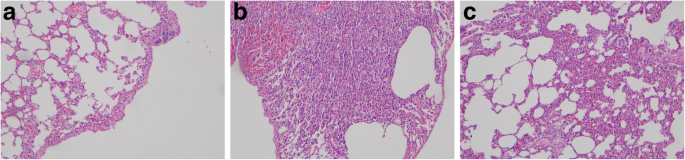

Evaluation of contralateral surfaces showed that both inflammation and fibrosis were absent from the parietal, visceral and mediastinal pleural surfaces, as well as the lung and diaphragm (Fig. 4).

Microscopic evaluations in the different groups. a: Sterile Talcum group; Development of fibrosis in the visceral pleura (arrow) and emphysematous changes in the subpleural area. H&E, × 100. b: Autologous blood transfusion group; Development of mild fibrosis in the visceral pleura around intense parenchymal inflammation areas (arrow). H&E, × 100. c: HES 130/0.4 (6%) group; Intense inflammatory response and mild emphysematous changes, H&E, × 100